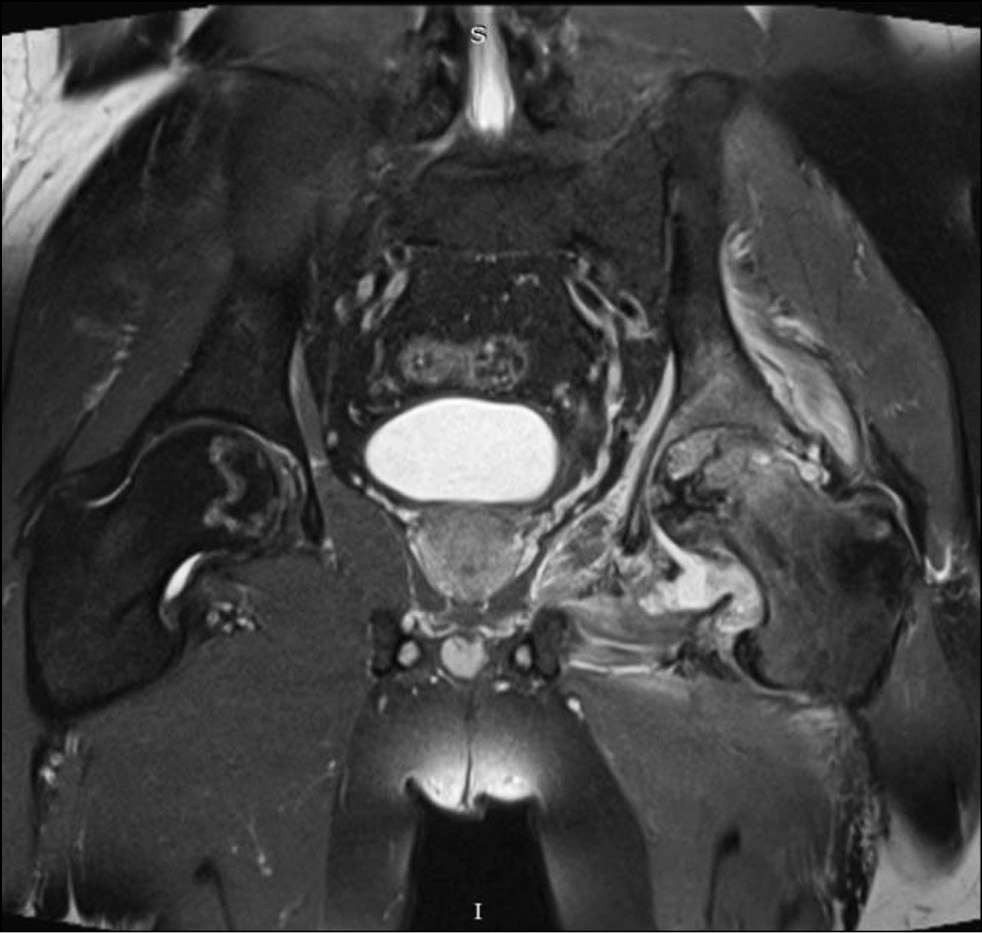

В марте 2023 года пациент был госпитализирован в хирургическое отделение № 2 клиники пропедевтической хирургии (отделение гнойной хирургии) клиник СамГМУ с подозрением на септический коксит слева, некроз головки левой бедренной кости. При поступлении уровень лейкоцитов составлял 11,3×109/л, СРБ — 97,3 мг/л, СОЭ — 24 мм/час. Дополнительные инструментальные исследования не выявили септических очагов иной локализации. При повторном проведении МРТ тазобедренных суставов были выявлены следующие изменения: резко выраженный синовит, выраженная гипертрофия суставной капсулы, отёк периартикулярных мягких тканей, не свойственные для типичной картины АНГБК (рис. 2).

Рис. 2. Предоперационная магнитно-резонансная томограмма тазобедренных суставов пациента С., 38 лет, в коронарной проекции.